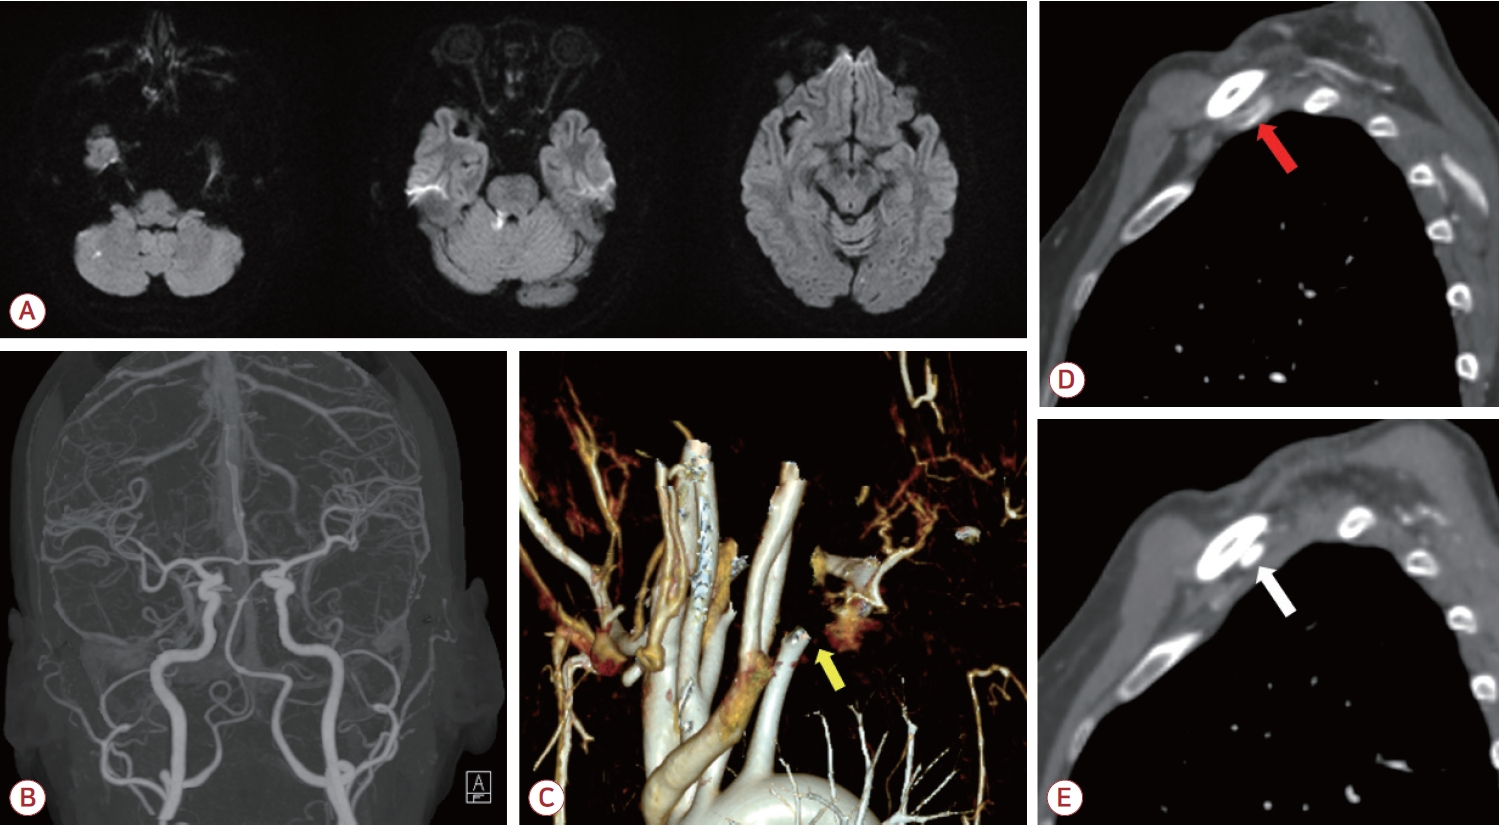

뇌자기공명영상의 확산강조영상(diffusion-weighted image) 에서는 우측 소뇌 및 소뇌다리, 좌측 후두엽에서 다발색전 양상의 고신호강도 병변이 보였다(Fig. 1-A). 또한 이후 시행한 뇌전산화단층촬영 혈관조영영상에서는 우측 척추동맥의 형성 저하 외에는 뇌내혈관 및 경동맥의 유의미한 협착은 관찰되지 않았다(Fig. 1-B). 또한 상지 전산화단층촬영혈관조영에서 쇄골하동맥의 폐색이 관찰되었으며(Fig. 1-C) 우측에 비해 좌측 쇄골과 경추늑골 사이 공간이 협소하고 혈류가 감소한 소견이 보였다(Fig 1-D, E). 혈액 검사상 D-이합체(D-dimer)는 3.21 μg/mL (정상, 0.0-0.5)로 상승되어 있었으며 항인지질인자, C/S단백질(protein C/S), 항트롬빈-III, 폰빌레브란트인자 등의 검사는 별도로 진행하지 않았다. 심전도, 경흉부 및 경식도심초음파, 24시간심전도 검사에서 심인성 색전증을 일으킬 수 있는 다른 질환은 발견되지 않았다.

환자는 좌측 쇄골하동맥 폐색 및 동반된 뇌경색에 대해 입원하여 저분자량헤파린인 에녹사파린(enoxaparin) 1 mg/kg 하루 두 번으로 항응고 치료를 시작하였고 입원 3일차에 쇄골하동맥의 혈전색전제거술(thromboembolectomy)을 시행하였다(Fig. 2-B). 시술 후에 환자는 추가적인 뇌경색 병변이 발견되지 않았고 좌측 상지의 청색증이 호전되었으며 혈압 또한 우측과 차이를 보이지 않았다. 이후 에픽사반(apixaban) 5 mg 하루 두 번으로 약물 교체 이후 퇴원하였다. 시술 3개월 이후 추적 관찰한 혈관조영에서 이전에 보였던 혈전은 모두 제거되었고 새로운 혈전이 발생하지 않았음을 확인하였다. 또한 좌측 경추 늑골과 쇄골에 의한 쇄골하동맥의 압박 소견 및 이로 인한 말초 동맥류가 관찰되었다(Fig. 2-A, C, D). 이에 환자는 aTOS로 인한 뇌경색으로 최종 진단할 수 있었다. 환자는 항혈소판제인 아스피린 하루 100 mg으로 약물을 교체하였다. 환자에게 흉곽 출구증후군에 대해 경추늑골제거술 및 혈관성형술 등 수술적 치료를 권유하였으나 거절하여 약물 복용 유지 중에 있다.

본 증례의 환자는 뇌경색 증상 이전에 우측 상지의 감각 증상 및 청색증이 나타났고 이후 어지러움 및 이명 등의 증상이 나타났다. 시행한 영상 검사에서는 뇌 후순환 영역의 여러 부위에 색전성 뇌경색 및 좌측 쇄골하동맥의 혈전 및 폐색이 확인되었다. 혈역학적으로 상소뇌동맥 및 전하소뇌동맥은 좌우 척추동맥이 합쳐져 형성된 뇌기저동맥에서 기시한다. 또한 환자의 우측 척추동맥저형성증을 고려할 때 좌측 척추동맥에서 공통 후하소뇌동맥이 분지하는 해부학적 변이가 존재할 가능성이 높다[8]. 이를 종합적으로 고려하면 우측 소뇌 영역을 포함한 뇌경색 병변은 좌측 쇄골하동맥 내 혈전이 색전의 기원으로 작용하였을 가능성이 높다고 판단하였다. 또한 추적 검사에서 경추 늑골의 쇄골하동맥 압박 및 쇄골하동맥류가 확인되어 aTOS 및 이로 인한 급성 뇌경색으로 진단할 수 있었다.